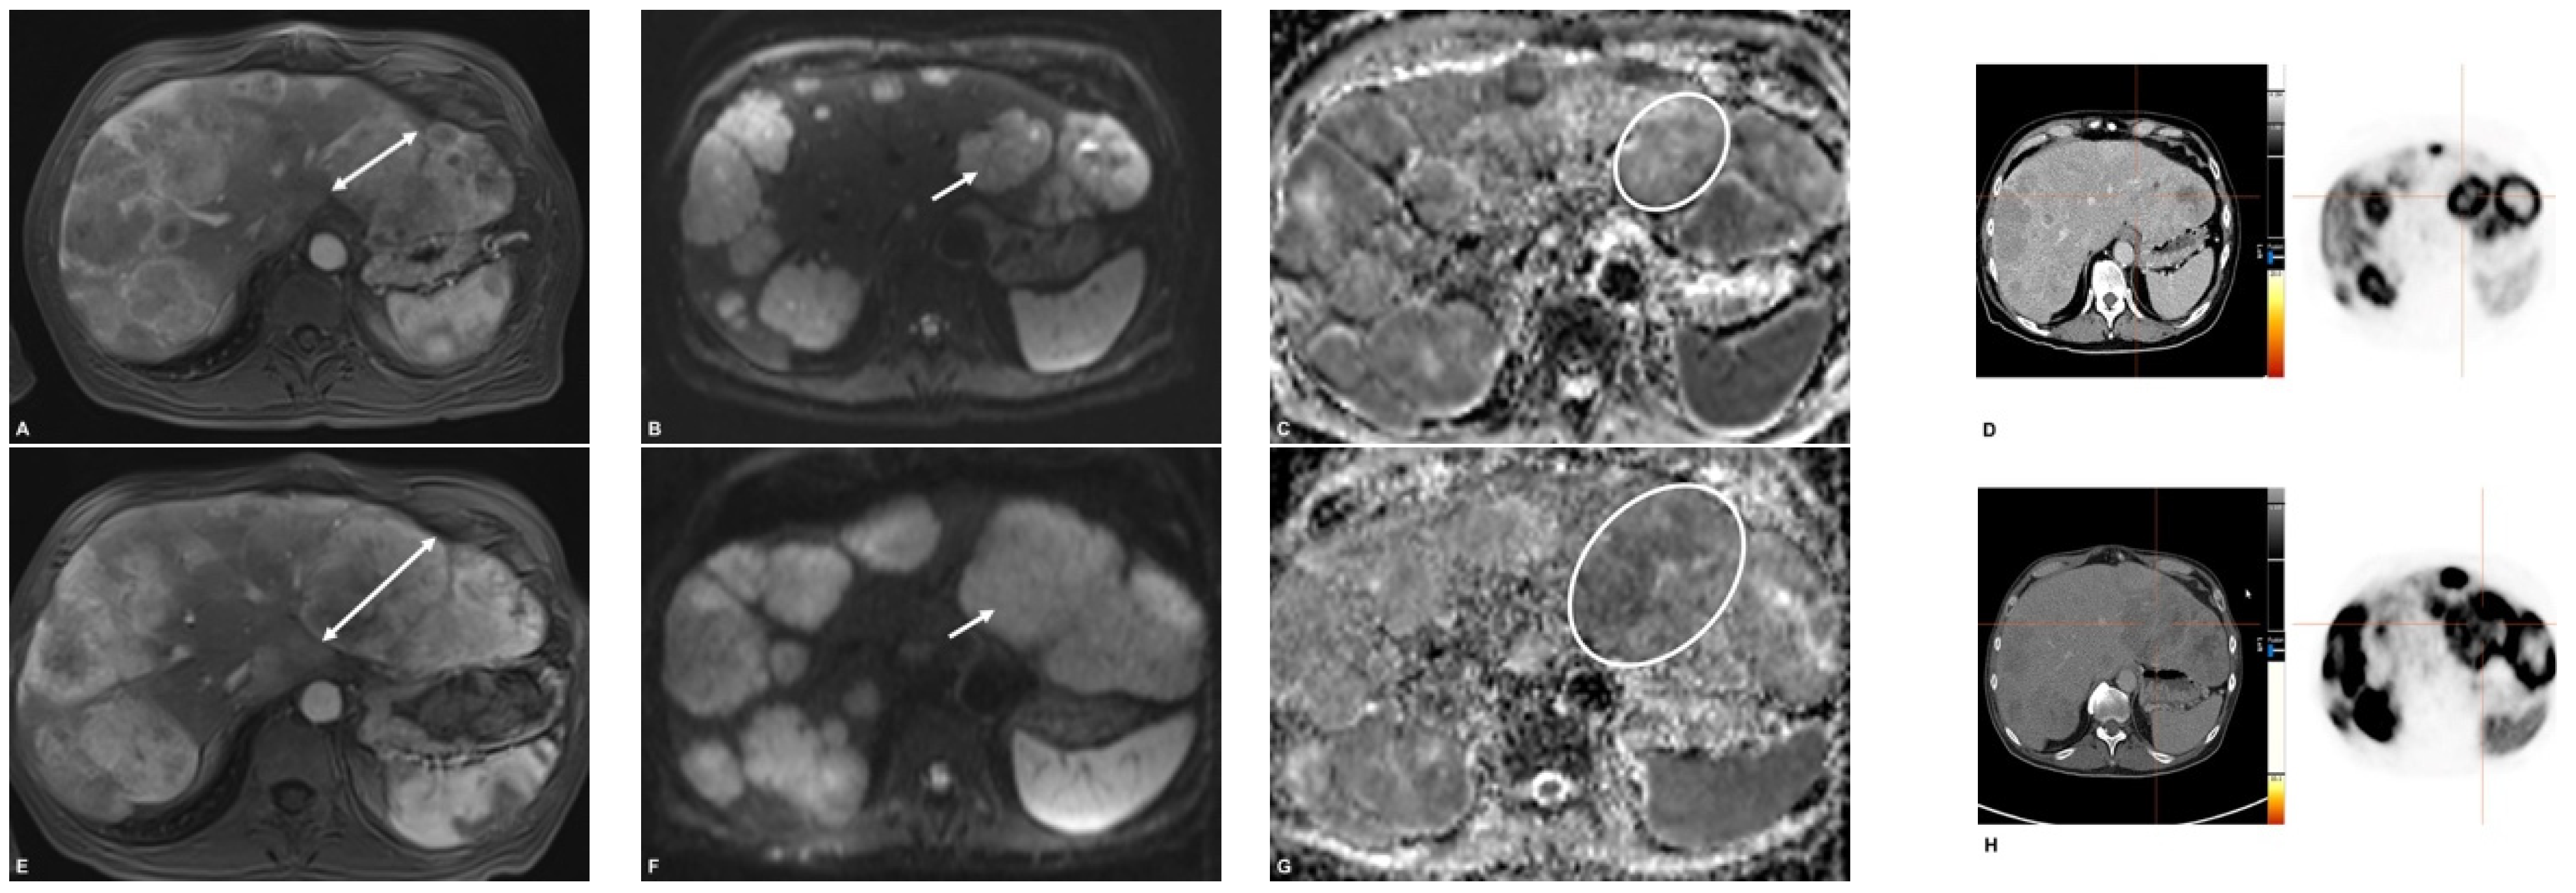

3.3. Response Assessment on First Follow-Up

3.4. Response According to HPFS > 6 Months

3.5. Response According to HPFS > 12 Months

3.6. Response According to HPFS > Median (720 d)